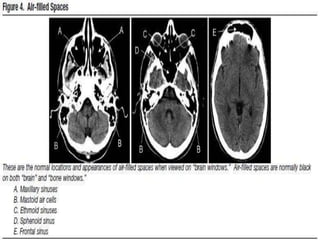

Hypodense

• Most commonly odema secondary to:

• Infection

• Inflamation.

• Stroke.

• Mass lesion.

• Fat containing structures.

• Air

• Paranasal sinuses and mastiod are structures that

are hypodense in normal cases.

Causes of air

• Air filled spaces.

• Base of the skull fracture.

• Craniotomy or after other surgeries

Hypodense • Most commonlyodema secondary to: • Infection • Inflamation. • Stroke. • Mass lesion. • Fat containing structures. • Air • Paranasal sinuses and mastiod are structures that are hypodense in normal cases.

Causes of air •Air filled spaces. • Base of the skull fracture. • Craniotomy or after other surgeries